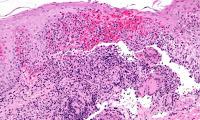

Los investigadores del Centro de Investigación Biomédica (BRC) de Guy y St Thomas de NIHR Universidad de Manchester, desarrollaron la técnica estudiando los glóbulos blancos tomados de pacientes con enfermedad de Crohn y comparándolos con células de personas sanas. Sus hallazgos permitieron a los especialistas en terapia celular en el BRC desarrollar un tratamiento que consiste en tomar las células de los pacientes y cultivarlos en un cultivo especial para que se comporten más como células de personas sanas. La investigación, publicada en la revista Gastroenterology , muestra que esta técnica es efectiva en células humanas , lo que significa que está lista para su uso en un ensayo clínico. El ensayo propuesto evaluará si el tratamiento es seguro y eficaz para tratar la enfermedad de Crohn. Los investigadores descubrieron que los glóbulos blancos especializados llamados células T reguladoras de los pacientes de Crohn producen menos de una proteína específica para el intestino llamada integrina α4β7 que las células T reguladoras de personas sanas. Trabajando con los especialistas de la Plataforma de Fabricación de Terapias Avanzadas de NIHR desarrollaron una técnica de terapia celular basada en estos hallazgos. Esta técnica consiste en desarrollar células de pacientes con enfermedad de Crohn con una molécula llamada RAR568, que restaura niveles saludables de integrina α4β7. Las células se devuelven a los pacientes mediante infusión intravenosa.

Los investigadores del Centro de Investigación Biomédica (BRC) de Guy y St Thomas de NIHR Universidad de Manchester, desarrollaron la técnica estudiando los glóbulos blancos tomados de pacientes con enfermedad de Crohn y comparándolos con células de personas sanas. Sus hallazgos permitieron a los especialistas en terapia celular en el BRC desarrollar un tratamiento que consiste en tomar las células de los pacientes y cultivarlos en un cultivo especial para que se comporten más como células de personas sanas. La investigación, publicada en la revista Gastroenterology , muestra que esta técnica es efectiva en células humanas , lo que significa que está lista para su uso en un ensayo clínico. El ensayo propuesto evaluará si el tratamiento es seguro y eficaz para tratar la enfermedad de Crohn. Los investigadores descubrieron que los glóbulos blancos especializados llamados células T reguladoras de los pacientes de Crohn producen menos de una proteína específica para el intestino llamada integrina α4β7 que las células T reguladoras de personas sanas. Trabajando con los especialistas de la Plataforma de Fabricación de Terapias Avanzadas de NIHR desarrollaron una técnica de terapia celular basada en estos hallazgos. Esta técnica consiste en desarrollar células de pacientes con enfermedad de Crohn con una molécula llamada RAR568, que restaura niveles saludables de integrina α4β7. Las células se devuelven a los pacientes mediante infusión intravenosa.

Los investigadores del Centro de Investigación Biomédica (BRC) de Guy y St Thomas de NIHR Universidad de Manchester, desarrollaron la técnica estudiando los glóbulos blancos tomados de pacientes con enfermedad de Crohn y comparándolos con células de personas sanas. Sus hallazgos permitieron a los especialistas en terapia celular en el BRC desarrollar un tratamiento que consiste en tomar las células de los pacientes y cultivarlos en un cultivo especial para que se comporten más como células de personas sanas. La investigación, publicada en la revista Gastroenterology , muestra que esta técnica es efectiva en células humanas , lo que significa que está lista para su uso en un ensayo clínico. El ensayo propuesto evaluará si el tratamiento es seguro y eficaz para tratar la enfermedad de Crohn. Los investigadores descubrieron que los glóbulos blancos especializados llamados células T reguladoras de los pacientes de Crohn producen menos de una proteína específica para el intestino llamada integrina α4β7 que las células T reguladoras de personas sanas. Trabajando con los especialistas de la Plataforma de Fabricación de Terapias Avanzadas de NIHR desarrollaron una técnica de terapia celular basada en estos hallazgos. Esta técnica consiste en desarrollar células de pacientes con enfermedad de Crohn con una molécula llamada RAR568, que restaura niveles saludables de integrina α4β7. Las células se devuelven a los pacientes mediante infusión intravenosa.

Los investigadores del Centro de Investigación Biomédica (BRC) de Guy y St Thomas de NIHR Universidad de Manchester, desarrollaron la técnica estudiando los glóbulos blancos tomados de pacientes con enfermedad de Crohn y comparándolos con células de personas sanas. Sus hallazgos permitieron a los especialistas en terapia celular en el BRC desarrollar un tratamiento que consiste en tomar las células de los pacientes y cultivarlos en un cultivo especial para que se comporten más como células de personas sanas. La investigación, publicada en la revista Gastroenterology , muestra que esta técnica es efectiva en células humanas , lo que significa que está lista para su uso en un ensayo clínico. El ensayo propuesto evaluará si el tratamiento es seguro y eficaz para tratar la enfermedad de Crohn. Los investigadores descubrieron que los glóbulos blancos especializados llamados células T reguladoras de los pacientes de Crohn producen menos de una proteína específica para el intestino llamada integrina α4β7 que las células T reguladoras de personas sanas. Trabajando con los especialistas de la Plataforma de Fabricación de Terapias Avanzadas de NIHR desarrollaron una técnica de terapia celular basada en estos hallazgos. Esta técnica consiste en desarrollar células de pacientes con enfermedad de Crohn con una molécula llamada RAR568, que restaura niveles saludables de integrina α4β7. Las células se devuelven a los pacientes mediante infusión intravenosa.